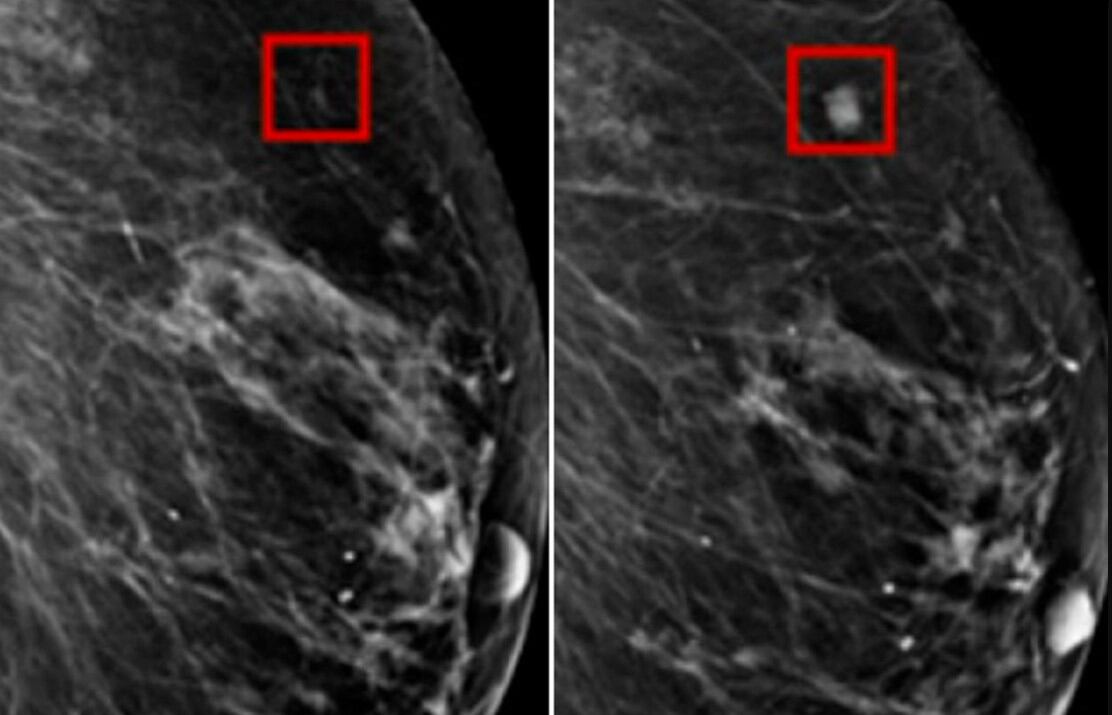

Dos radiólogos habían dicho previamente que la radiografía no mostraba ningún signo de que la paciente tuviera cáncer de mama. Pero Ambrózay estaba observando de cerca varias áreas del escaneo marcadas con un círculo rojo, que el software de inteligencia artificial había marcado como potencialmente cancerosas.

La IA, llamada Detección Asistida por Computadora, identifica manchas en las mamografías para que los médicos las inspeccionen de cerca.

Un estudio asociado del Instituto Tecnológico de Massachusetts (MIT) descubrió que la tecnología podía identificar cambios entre mamografías y detectar puntos que tenían riesgo de convertirse en cáncer. Los puntos identificados en pacientes se convirtieron en cáncer de mama años después.